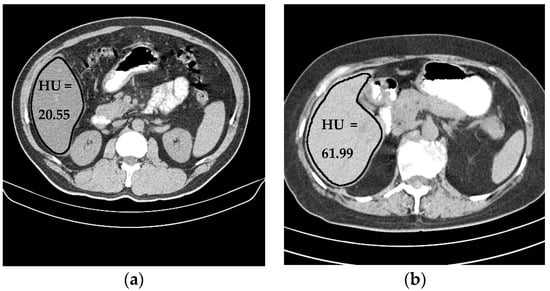

Liver density is inversely related to liver fat, according to Ricci et al. [7]. The mean of the liver HU values for the used data set was employed as an indicator for the level of diffused fat in the liver. Figure 13 illustrates two examples of two CT images (two different subjects) where the liver is bounded by black contours using the proposed liver segmentation method. The liver in each example shows different tissue densities.

Figure 13. Variation of liver HU values. (a) Low HU value, (b) high HU value.